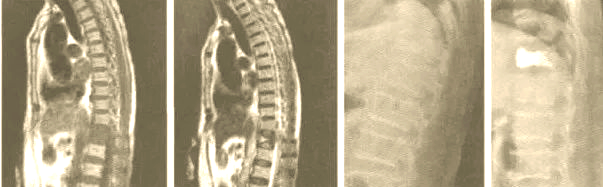

症状性胸腰段椎间盘突出为休门氏病的特殊表现

图片尺寸566x736

中间图符合腰型休门氏病标准.右图符合典型休门氏病标准.

图片尺寸1000x568